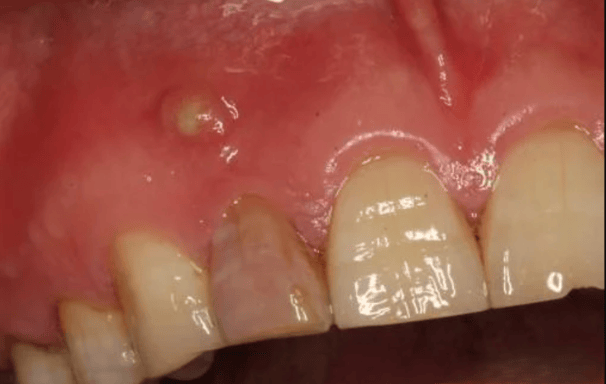

Se trata infecciones o abscesos que se forman en el tejido alrededor de la raíz del diente. Este tratamiento busca eliminar la infección y preservar el diente

Tratamiento de lesiones periapicales

Tratamiento de abscesos dentales

Se trata de una infección en el extremo de la raíz del diente que forma una acumulación de pus. El tratamiento incluye la limpieza y desinfección del conducto radicular y, en algunos casos, el drenaje del absceso.

Tratamiento de Absceso Periapical

Es una inflamación crónica en el extremo de la raíz del diente que forma una masa de tejido. El tratamiento incluye la eliminación del tejido infectado mediante un tratamiento de conducto y, en casos severos, cirugía apical

Tratamiento de Granuloma Apical